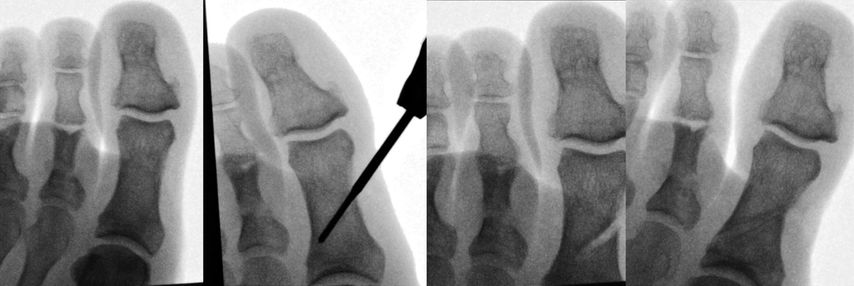

Auch die Akin-Osteotomie kann sehr einfach minimalinvasiv durchgeführt werden. Sie wird entweder mit einer Schraube oder aber einfach mit Tapes für 4 Wochen stabilisiert (Abb. 2).